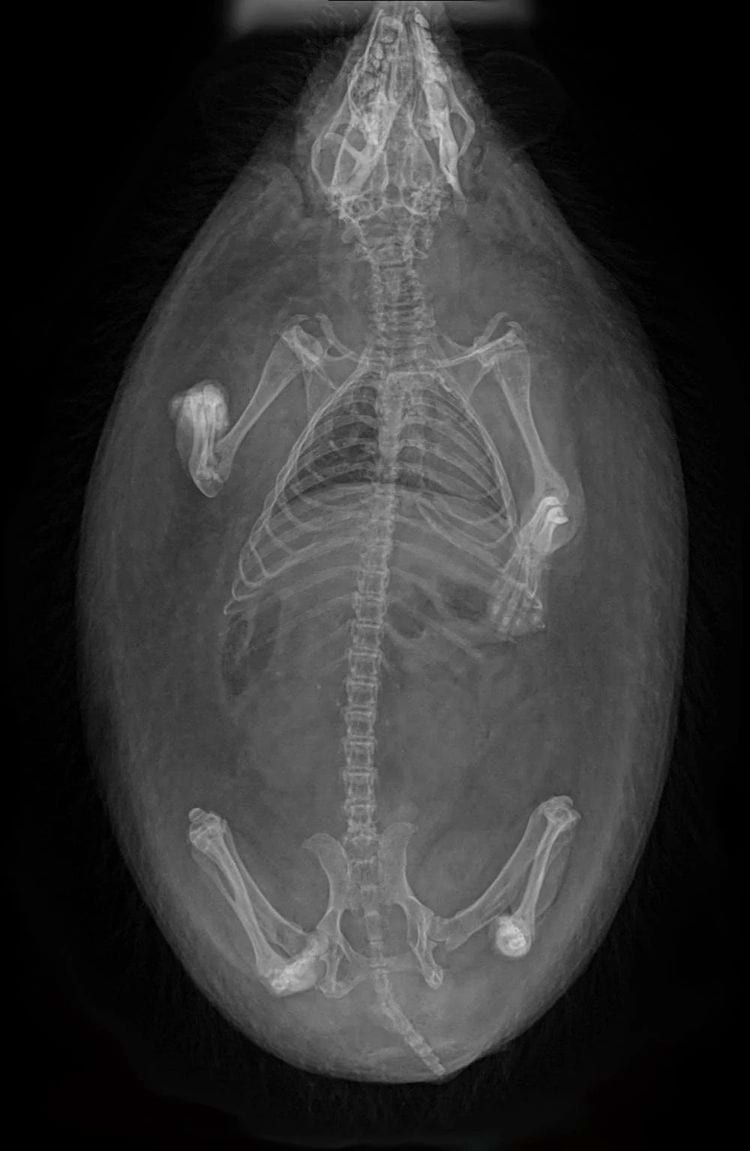

«Рентгенограмма моего ёжика»